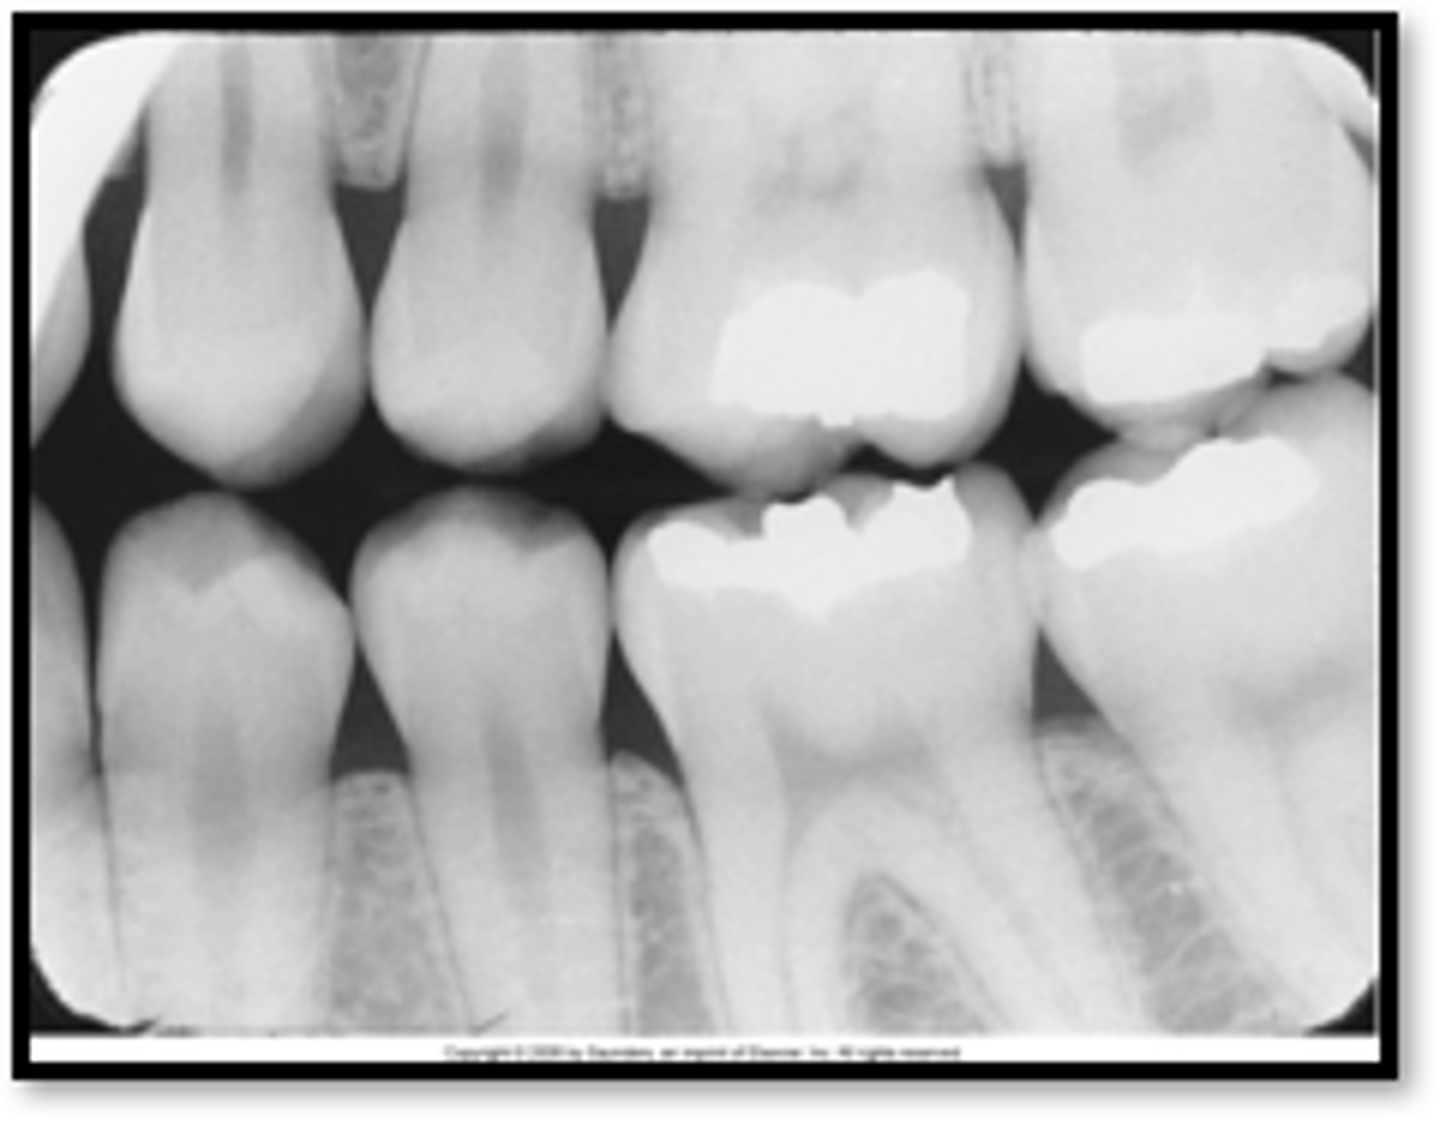

porcelain fused to metal radiograph

porcelain fused to metal image

cubic zirconium

composite

full gold crown with pins

all porcelain crown